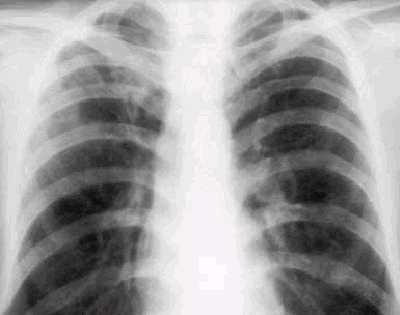

Рис. 1. Больной Ш., 19 лет. Обзорная рентгенограмма.

Очаговый туберкулез. Справа в подключичной зоне на фоне фиброзных изменений определяются множественные очаги средней плотности